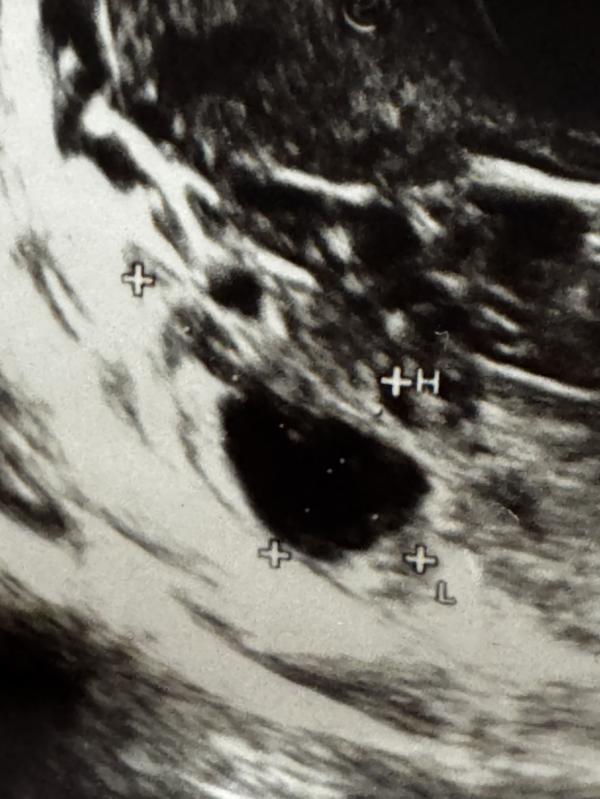

Хелп! Как вы думаете на фото фолликул несовулировавший или все таки желтое тело? 🧐

Скорее ЖТ, чем фолликул…